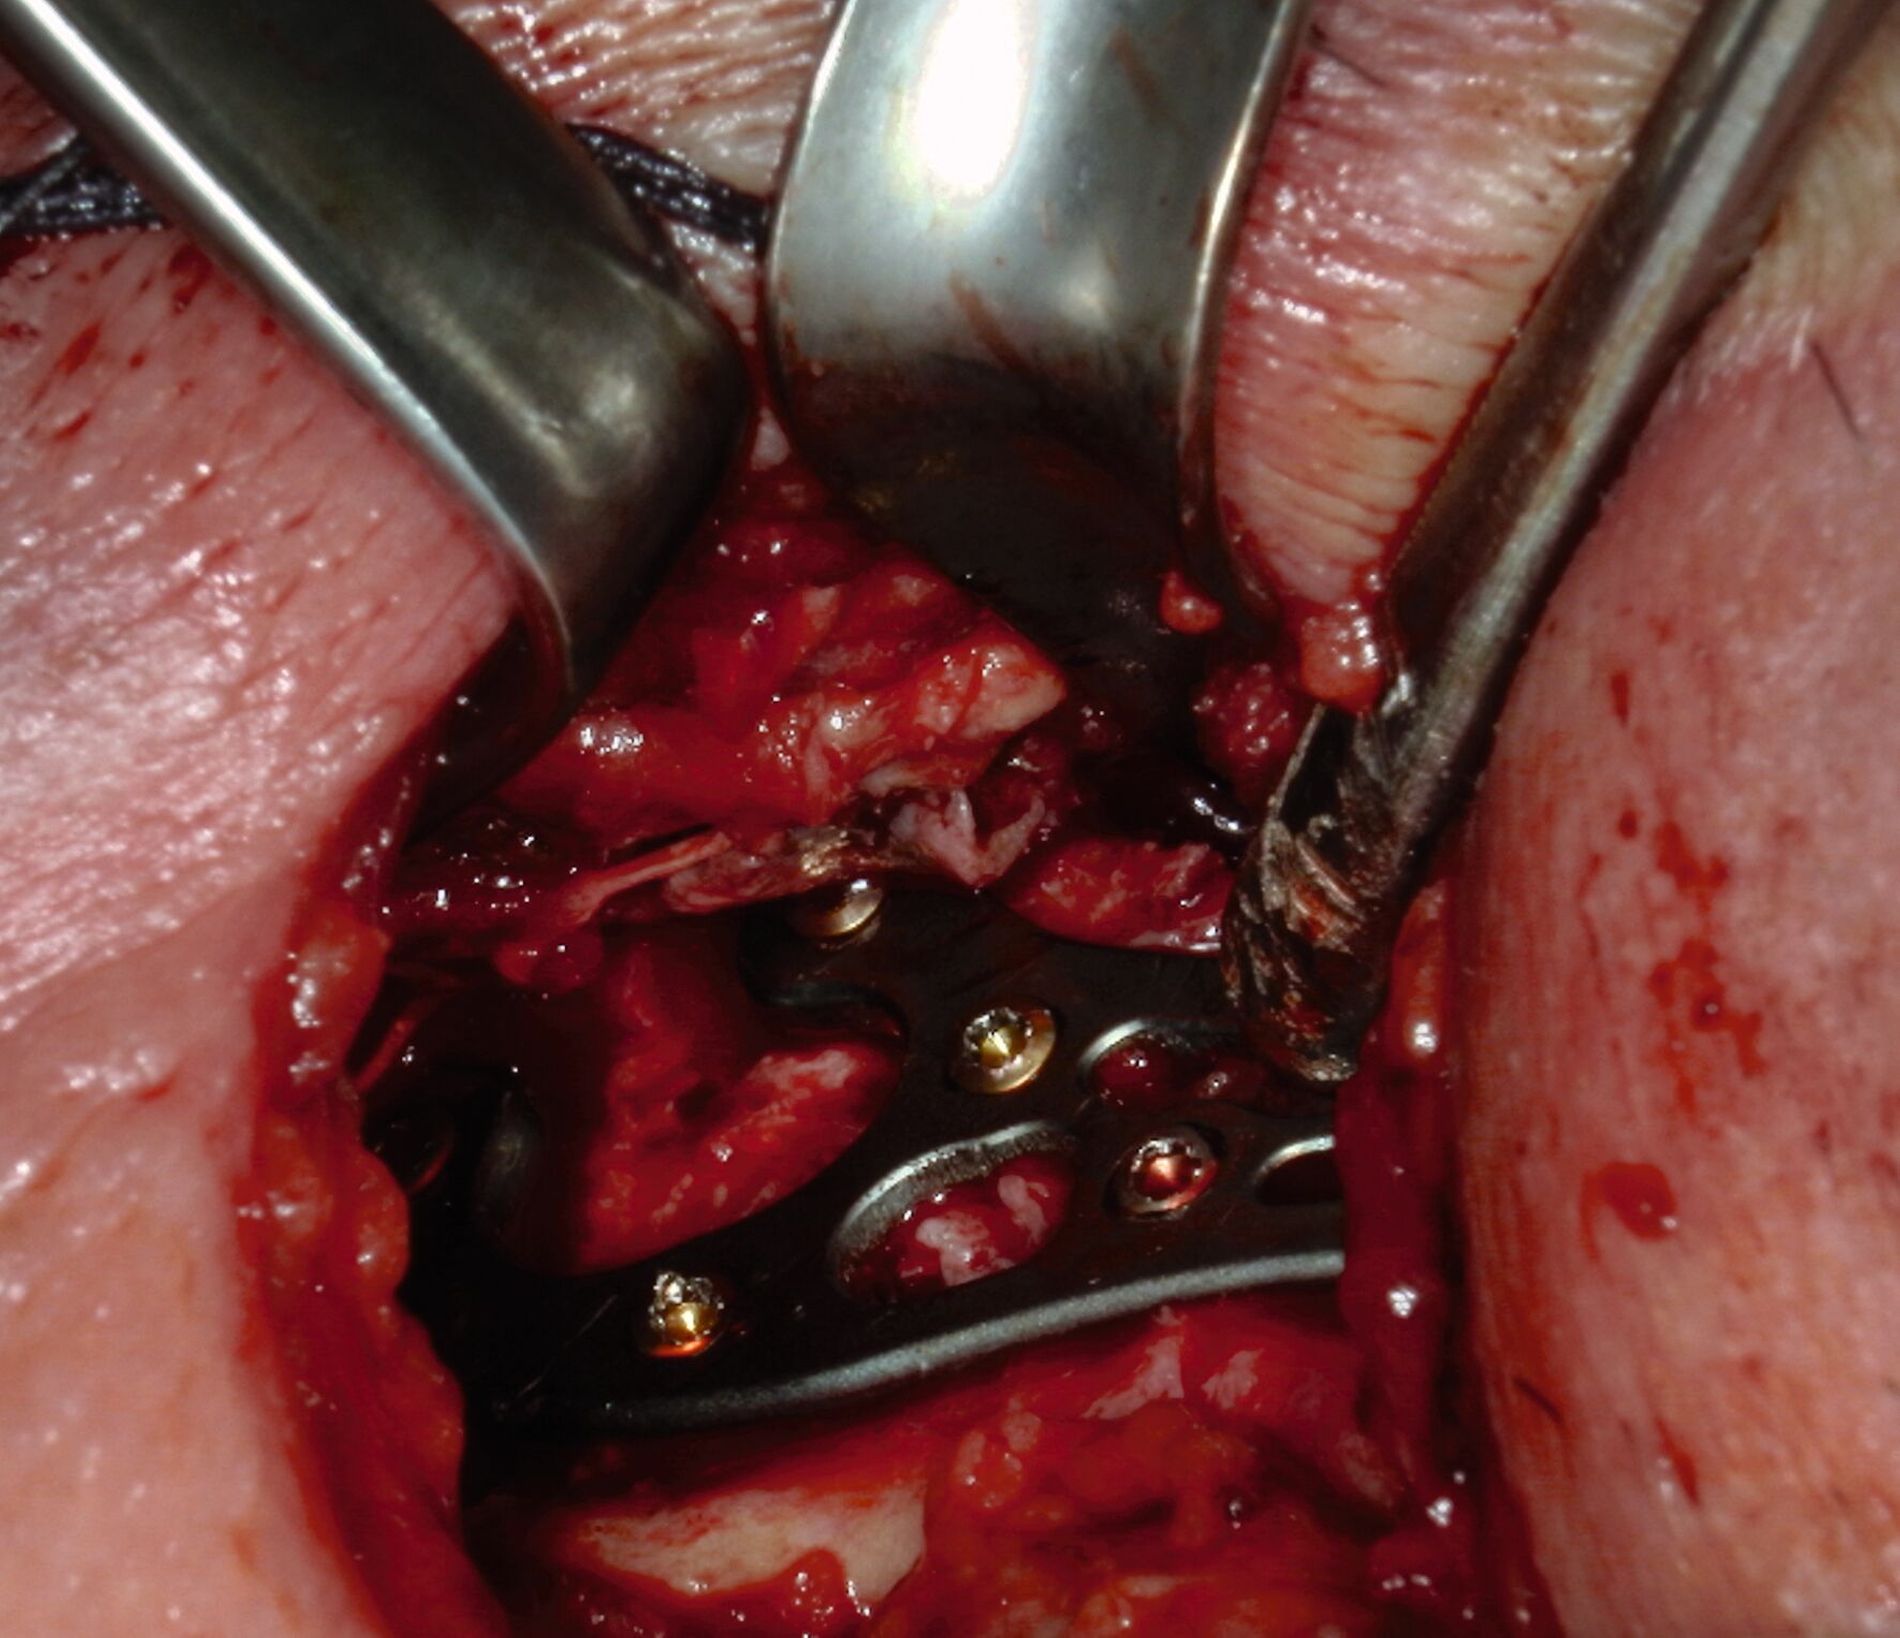

Intraoperativ wurde die Kontinuitätsresektion des Unterkiefers gemäß der präoperativen Planung vom Kieferwinkel bis knapp unterhalb der Incisura semilunaris über einen rein extraoralen Zugang durchgeführt, wobei der Nervus alveolaris inferior dargestellt und geschont wurde. Entscheidend war in diesem Fall, dass es zu keinem Zeitpunkt zu einer Eröffnung des Operationssitus nach enoral kam, wodurch eine Kontamination des avaskulären Knochens durch Speichel oder Speisereste vollständig vermieden werden konnte. Unsere klinische Erfahrung zeigt, dass eine solche Perforation, ebenso wie die Notwendigkeit einer Hautinsel, eine mikrovaskuläre Rekonstruktion dringend erforderlich gemacht hätte.

Danach wurde ein avaskuläres Beckenkammtransplantat vom rechten Becken entnommen. Die Auswahl eines avaskulären Knochentransplantats wurde aufgrund der klinischen Umstände und der präoperativen Planung bevorzugt, um eine möglichst schonende und risikoarme Vorgehensweise zu gewährleisten. Das Transplantat wurde anschließend in regelhafter Okklusion mittels präformierter Rekonstruktionsplatte eingebracht und osteosynthetisch fixiert. (Abbildungen 2 und 3).